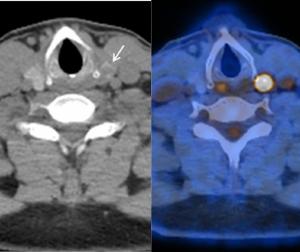

Can PET/CT Bolster Malignancy Detection with Thyroid Incidentalomas?